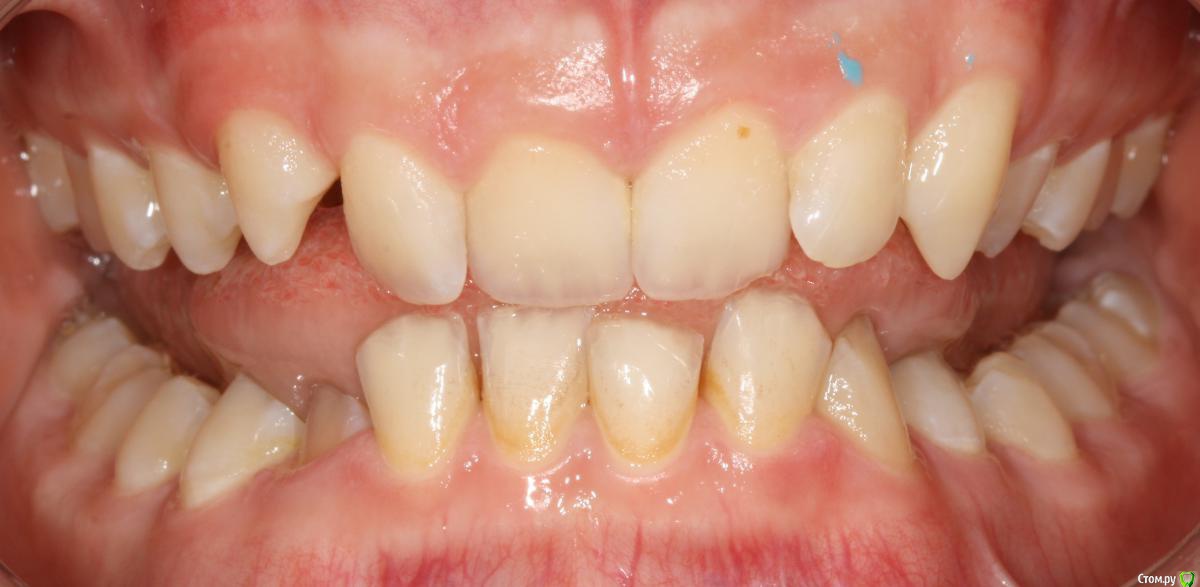

Opdihatop Опубликовано 24 октября, 2017 Поделиться Опубликовано 24 октября, 2017 И еще раз здравствуйте! Сразу хочу презентовать еще одного мальчика. Лично я такого еще не видел, а потому хочу понять, что тут делать. Думаю, невооруженным взглядом видно гипертонус и гиперплазию массетеров и гиперплазию углов н/ч из-за этого. Из-за чего это может быть и что тут делать? Как расслабить и что вообще делать с мышцами? Слать ли на сцинтиграфию (мало ли, может рост продолжается)? Есть ли шанс повысить прикус или такие мышцы все равно вколотят? Члх или нет? Заранее спасибо! Ссылка на комментарий

krokomot Опубликовано 24 октября, 2017 Поделиться Опубликовано 24 октября, 2017 Ботокс хорошо расслабляет, в данной ситуации, следует дифференцировать от остеодисплазии, херувизма. 1 Ссылка на комментарий

Brigita Опубликовано 25 октября, 2017 Поделиться Опубликовано 25 октября, 2017 (изменено) дифференцировать от остеодисплазии, херувизма.точно не херувизм. там в полости рта другая картина совсем, а по поводу дисплазии - она чаще односторонняя, может быть.... Изменено 25 октября, 2017 пользователем Brigita Ссылка на комментарий

krokomot Опубликовано 25 октября, 2017 Поделиться Опубликовано 25 октября, 2017 Выкладывайте кт, сильно сомневаюсь что повышенный тонус массетер привел к гиперплазии углов. Перестройка да, гиперплазия нет. Ссылка на комментарий